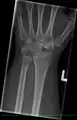

Left hand x-ray post proximal row carpectomy